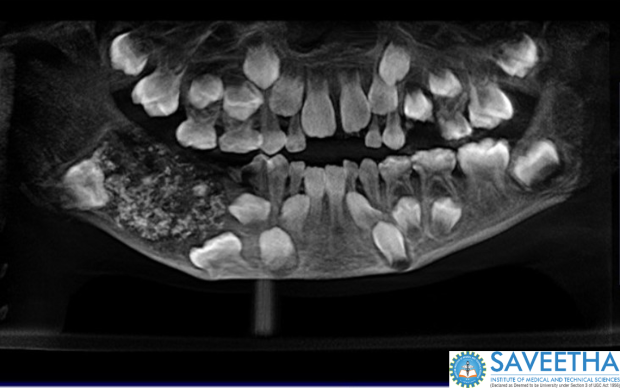

A 7-year-old boy in India had a legion of teeth removed from his mouth — 526 teeth, to be exact. The unusual surgery was performed at Saveetha Dental College and Hospital in Chennai, India.

The boy was brought to the hospital with swelling in his lower right jaw, and he was found to be suffering from "compound composite ondontome," according to a press release from the hospital.

When he came back at age 7, his parents worried that he might have cancer in his jaw. The doctors decided to operate, and found what they described as a "bag like mass, which was removed in its entirety," according to the press release. The sack weighed almost half a pound. Inside were 526 tooth-like structures.

They ranged in size from 1mm to 15mm and resembled a tooth with a crown covered by enamel and a root-like structure. It was unlike anything the doctors had seen before. "This pandora box of miniature teeth is a jewel on our crown," doctors said.